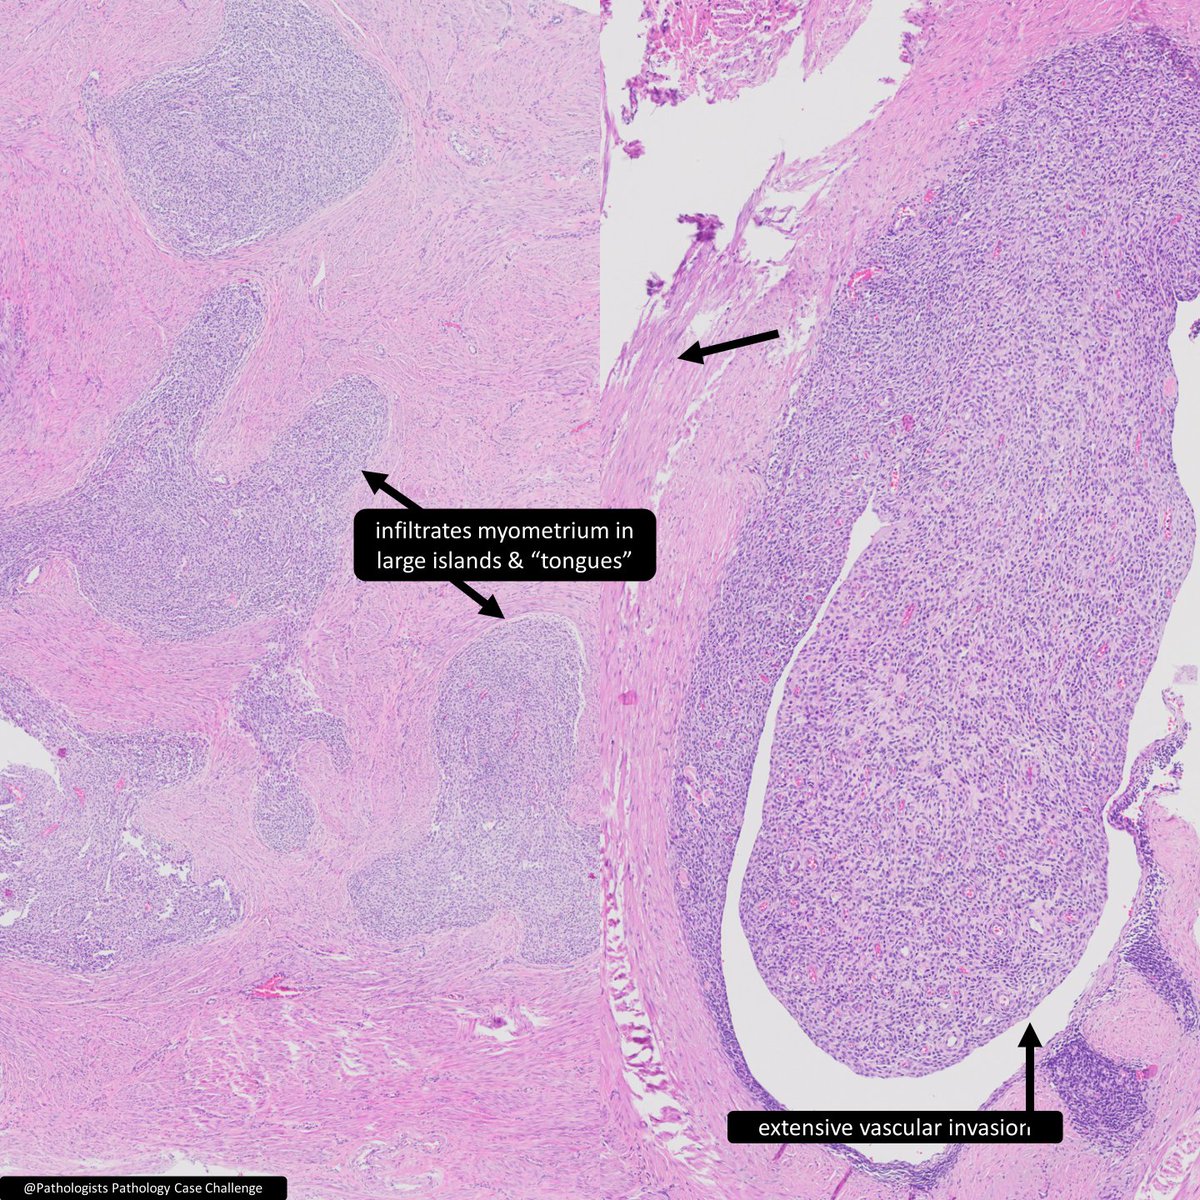

Endometrial stromal ___ a) nodule b) sarcoma 🔬@Pathologists https://t.co/1z7GBOsejY #GYNPath #PathTwitter #Pathology #BSTPath